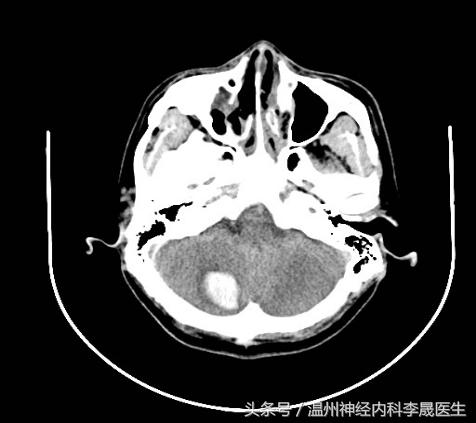

小脑脑叶出血

小脑蚓部出血